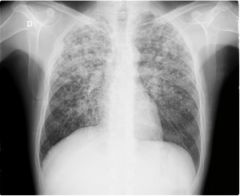

Cara mendeteksi gejala flek paru pada anak 3 tahun seperti yang telah kita tahu penyebab tuberkulosis adalah infeksi kronis dari virus yang bisa ditularkan dari tubuh si penderita sebelumnya. Obat herbal pembersih flek paru pada bayi dan anak dengan qnc jelly gamat telah efektif dan terbukti ampuh secara alami menyembuhkan tuberkulosis atau flek paru 100 aman tanpa efek samping. Tes untuk menentukan seseorang mengalami flek paru paru adalah serangkaian tes yang panjang dan cukup lama yang terdiri atas pemeriksaan bakteri pemeriksaan dahak pemeriksaan radiologis pemeriksaan darah dan tes uji tuberkulin. Berikut adalah gejala gejala yang umum ditemukan ketika tuberkulosis terjadi pada anak. Pada bayi gejala batuk mungkin tidak terlalu jelas. Berbeda dengan orang dewasa yang gejala utamanya batuk lama gejala pertama tbc pada anak yang dikenali orangtua adalah pertumbuhan anak yang lebih kecil dari seusianya.